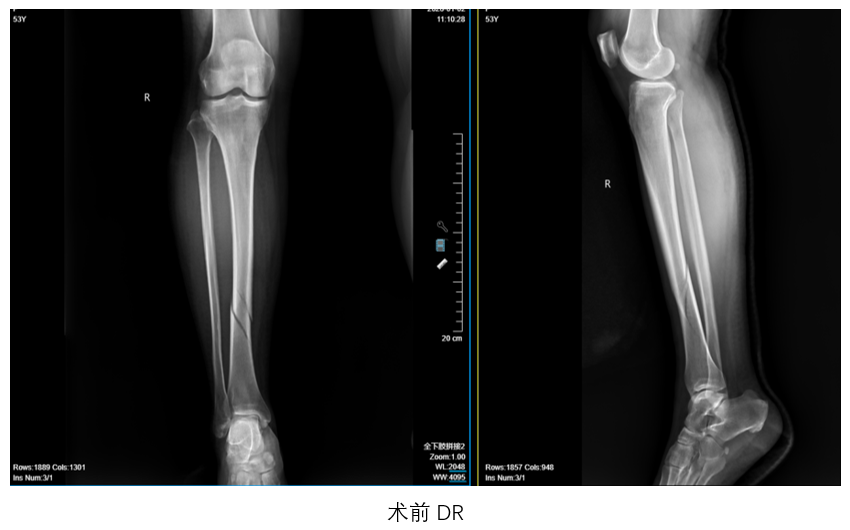

患者张某因骑电动车摔倒致右小腿肿痛、活动受限,于2026年1月1日入院,经诊断为“右侧胫骨骨折”。依托我院数智骨科平台,数智骨科团队制定个性化手术方案,术前通过高精度CT三维重建数据,虚拟模拟骨折复位路径,并设计个性化3D打印支具导板,该支具导板兼具引导复位、术中固定、穿针导航及后期康复等功能。

胫腓骨骨折传统手术依赖术者经验,且并发症风险较高。本次案例通过数字化诊疗全流程(术前规划-术中导航-智能康复),为闭合性胫骨骨折提供了精准化、标准化解决方案,有望在基层医院推广,惠及更多患者。